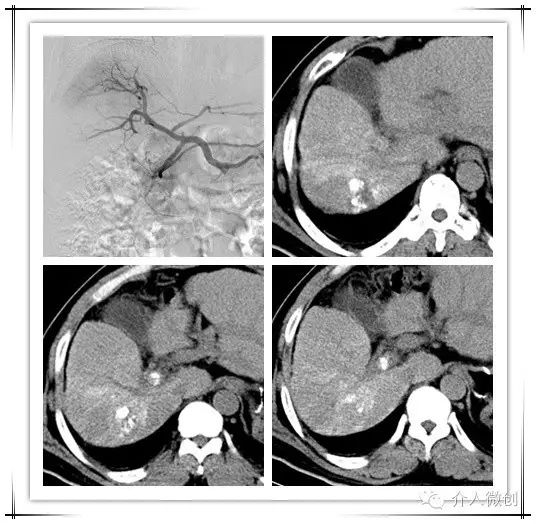

中年男性患者,诊断为原发性肝癌并门脉右支癌栓,术前甲胎蛋白升高(AFP:484ug/ml)。先予以行肝动脉化疗栓塞术(TACE),术后复查CT提示肝内病灶部分碘油沉积,门脉右支癌栓亦可见碘油沉积。

术前术后影像对比